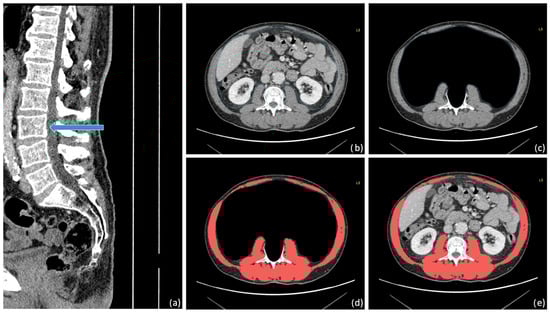

Background: Total tumor volume (TTV), derived from imaging data, has emerged as a potential prognostic biomarker in various cancers. This study aimed to evaluate the impact of TTV on outcomes in advanced pancreatic ductal adenocarcinoma (PDAC) and to validate a survival prediction model combining TTV with baseline clinico-biological markers. Materials and Methods: We conducted a retrospective analysis of 150 patients with locally advanced or metastatic PDAC treated with first-line FOLFIRINOX from 2010 to 2021. TTV was calculated by manually segmenting all visible lesions on baseline CT scans. Progression-free survival (PFS) and overall survival (OS) were the primary endpoints. A cut-off value for TTV predicting 6-month PFS was determined in 140 patients using AUC and Youden’s Index and then applied to OS analysis. A multivariate Cox regression model incorporating TTV, CA 19-9, and neutrophil-to-lymphocyte ratio (NLR) was developed in 94 patients to establish a survival risk score. Results: 12,028 lesions were annotated. OS was slightly but significantly different between TTV above and below the median value of 69.60 cm3 (12.4 vs. 13.5 months, p = 0.0269). A cut-off of 400 cm3 distinguished two groups: patients with TTV > 400 cm3 had significantly shorter OS (9.4 months) compared to those with TTV ≤ 400 cm3 (13.0 months, p = 0.0056). A similar trend was observed for PFS, though not statistically significant (7.4 months for TTV > 400 cm3 vs. 8.2 months for TTV ≤ 400 cm3, p = 0.0735). The combined model achieved a mean c-index of 0.62 for PFS and 0.64 for OS. Based on the risk score, high-risk patients had significantly worse median PFS (5.5 vs. 9.2 months, p = 0.0008) and median OS (7.2 vs. 13.5 months, p < 0.0001). Conclusions: TTV is a valuable prognostic marker in advanced PDAC. A model integrating TTV with biological markers enhances survival prediction and supports risk stratification in clinical practice.